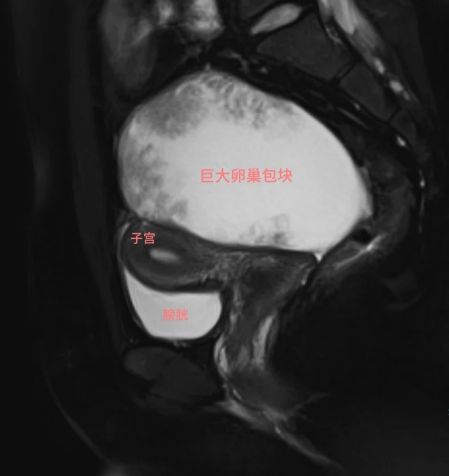

盆腔MRI影像

目前盆腔MRI和全腹CT提示,卵巢上皮来源恶性肿瘤的可能性较大,但还没发现明显转移灶,或许还有保留生育功能的机会。